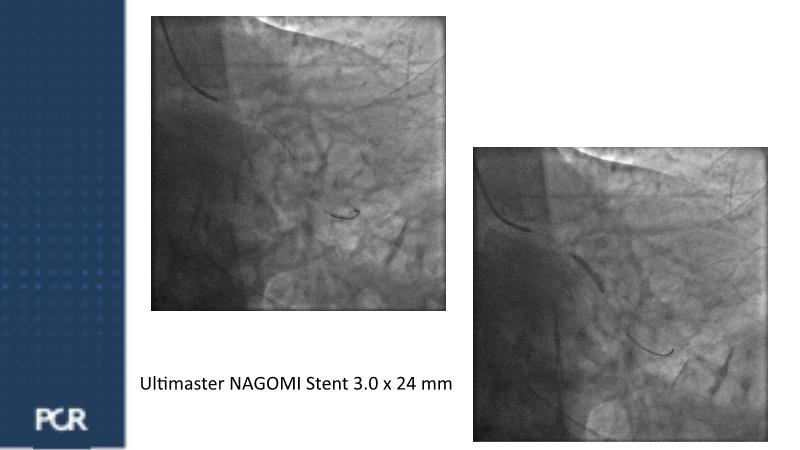

Watch this session for insights into managing acute coronary syndrome patients with multivessel disease, updates on treatment approaches, comparing FULL RESVAC with previous trials like COMPLETE or FIRE, for example, and information on ongoing trials such as FRAMI-AMI 2 and 3. Explore the LIVE case presentation for tailored strategies in post-ACS multivessel disease management, approaches for high bleeding risk patients, and the role of intracoronary imaging in guiding procedures.